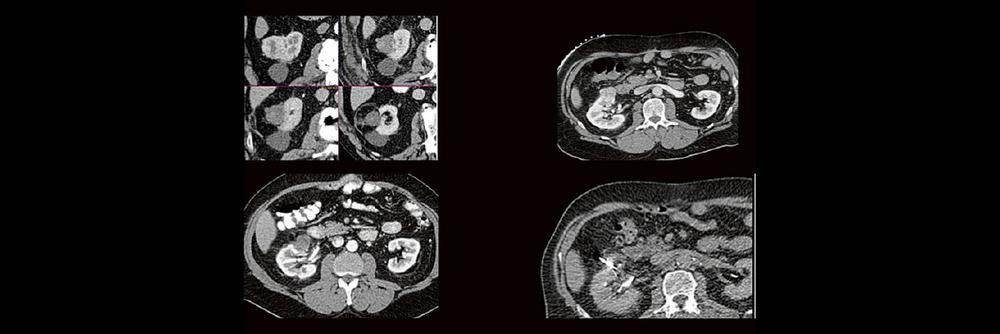

Thermoablation von Nierentumoren (Webinar | Online)

Dr. med. Sascha Alexander Pietruschka Die Anwendung von ablativen Verfahren hat sich in der klinischen Praxis etabliert. Nierentumoren bieten sich für den Einsatz von RFA und Mikrowelle an. Im Dietrich Bonhoeffer Klinikum Neubrandenburg blicken wir auf 15 Jahre Erfahrung mit mehr als 100 RFA/Mikrowellenablationen von Nierentumoren zurück. Im Vortrag werden die eigenen Erfahrungen und Ergebnisse […]